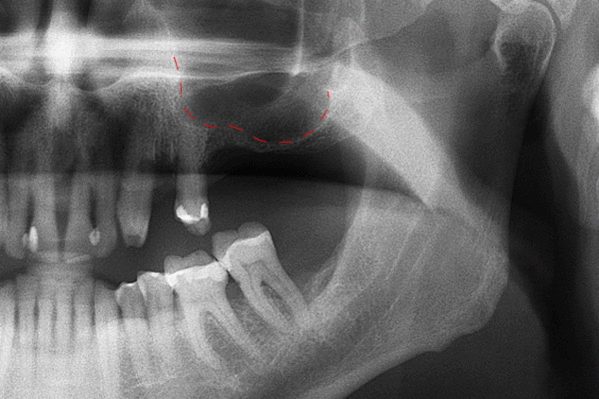

В дальнейшем обязателен ежегодный осмотр специалистом, в процессе которого:

- с помощью рентгенографии изучаются качество и плотность костной ткани;